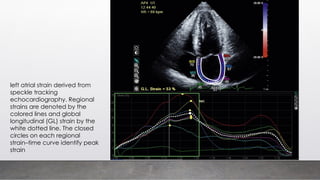

left atrial strain derived from

speckle tracking

echocardiography. Regional

strains are denoted by the

colored lines and global

longitudinal (GL) strain by the

white dotted line. The closed

circles on each regional

strain–time curve identify peak

strain